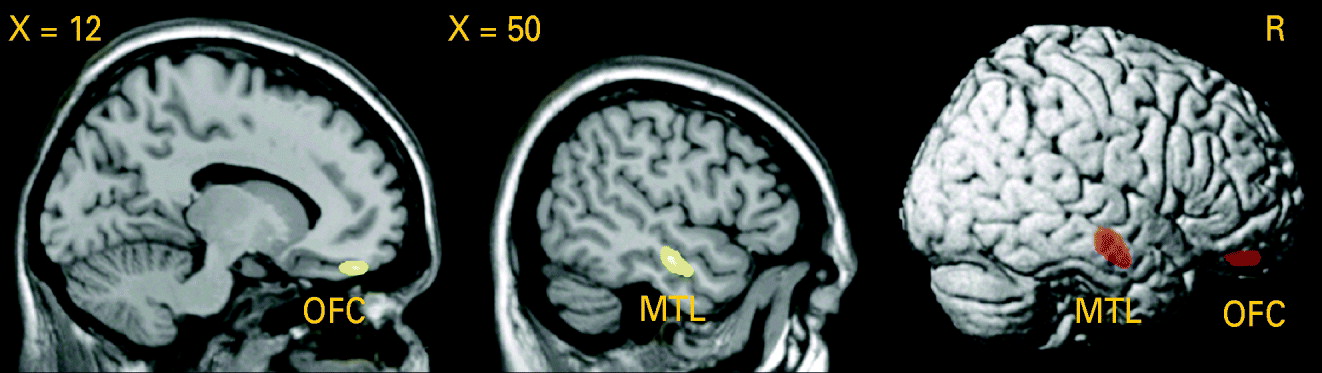

Testing the difference in GM volume between patients and healthy controls, we detected a significant GM volume reduction in the right middle temporal gyrus [Brodmann area (BA) 21: x=50, y=−15, z=−16, p (voxel-level)<0.001, k=1.56 cm3, p (cluster-level corrected)=0.01] in patients with PD, as shown in Fig. 3. Lowering the cluster-level threshold to the number of expected voxels per cluster, we detected an additional GM volume reduction in the medial part of the orbitofrontal cortex [BA 11: x=14, y=45, z=−20, p (voxel-level)<0.001, k=0.43 cm3, p (cluster-level corrected)=0.22; see Fig. 3). We did not observe any significant differences in the AHC and in the opposite contrast.

Fig. 3. Analysis using voxel-based morphometry (VBM): reduction of grey matter (GM) volume in patients with panic disorder (PD) relative to healthy controls (HC), voxel-level threshold: p<0.001 (uncorrected). Middle temporal lobe (MTL): p [cluster-level family-wise error (FWE) corrected]=0.01. Orbitofrontal cortex (OFC): cluster-level corrected according to the expected voxels per cluster.

When correlating the first eigenvariate (main component of the principal component analysis) extracted from the clusters of the significant GM difference in the middle temporal lobe and in the orbitofrontal cortex and the age at onset or duration of illness in patients with PD, there was a significant negative association between GM volume in the orbitofrontal cortex and the age at onset (r=−0.054, p=0.02).

The major findings of this quantitative volumetric and voxel-based morphometric MRI study were: a bilateral decrease in temporal lobe volume and a decrease in right frontal lobe volume in patients with PD. By means of VBM we were able to assess the abnormalities more precisely and detected significant GM volume reductions in the right middle temporal gyrus (BA 21) and in the medial part of the orbitofrontal cortex (BA 11).

In this study VBM analysis revealed a significant GM volume reduction in the right middle temporal gyrus and enabled the quantitative volumetric findings to be localized more precisely. Normal VBM results on the opposite side may indicate that abnormalities in the left temporal lobe are less pronounced or less specific. This point of view is also supported by the quantitative volumetric data: a volume decrease of the temporal lobe had a higher level of statistical significance on the right side (p<0.001) compared to the left (p<0.03). When comparing quantitative volumetry and VBM, it should be taken into account that both methods deal with different measures of volume and therefore may provide inhomogeneous or even disparate results. However, consistent findings can be expected if the effects are robust and specific. Up to now only one VBM study has been published with patients suffering from PD. Massana et al. (Reference Massana, Serra-Grabulosa, Salgado-Pineda, Gasto, Junque, Massana and Mercader2003a), by means of SPM99, reported GM deficits in the left parahippocampal gyrus of patients with PD on the threshold corrected for multiple comparisons. When using uncorrected p values (p<0.001), GM deficits could also be observed in the right middle temporal gyrus, which is in agreement with the results of the present study.

The frontal lobe in PD has not previously been investigated by quantitative volumetric MRI, although structural and functional neuroimaging studies have demonstrated striking abnormalities in this region. A decrease in right frontal lobe volume as assessed in this study is therefore a de novo finding, not comparable to any prior results. Subsequent VBM analysis revealed a significant GM volume reduction in the medial part of the orbitofrontal cortex. A possible reason that Massana et al. (Reference Massana, Serra-Grabulosa, Salgado-Pineda, Gasto, Junque, Massana and Mercader2003a) did not find any frontal lobe abnormalities is that they used a less advanced VBM approach based on SPM99.

Our results lend further support to current aetiological models of PD (Gorman et al. Reference Gorman, Kent, Sullivan and Coplan2000). Earlier observations of aberrant function of the orbitofrontal cortex in PD (Kent et al. Reference Kent, Coplan, Mawlawi, Martinez, Browne, Slifstein, Martinez, Abi-Dargham, Laruelle and Gorman2005) are substantiated and extended by our finding of a structural brain consequence of weakened ‘top-down governance’ of the orbitofrontal cortex in PD. With regard to the temporal lobe, as in most prior studies we did not find any abnormalities of the amygdala and hippocampus. Therefore, the important role of the medial temporal lobe in the pathophysiology of PD as it has been proposed could not be proved. However, our study revealed GM deficits in BA 21, a region that is involved in visual integration and contextual organization (Konen & Kastner, Reference Konen and Kastner2008). It might be that dysfunction in this area underlies psychopathological symptoms such as derealization and depersonalization, which often occur in PD. With this background, it is of interest that patients with DSM-IV depersonalization disorder exhibit lower metabolic activity in right BA 21 and 22 compared to normal controls (Simeon et al. Reference Simeon, Guralnik, Hazlett, Spiegel-Cohen, Hollander and Buchsbaum2000).

Nevertheless, the exact pathogenetic implications of the structural alterations remain unclear. The GM deficits in the medial orbitofrontal cortex and middle temporal gyrus as observed in our study proved to be correlated with age of onset but not with duration of illness. This result was unexpected. The structural abnormalities do not therefore seem to be a direct consequence of the disease process. As a possible explanation for this finding, it may be assumed that older individuals, when affected by PD, are more susceptible to neurostructural and neurofunctional abnormalities, possibly resulting in a more severe and chronic form of the disease. To answer these open questions, our findings need to be replicated by other VBM studies, and follow-up studies during the course of the disease should be performed.